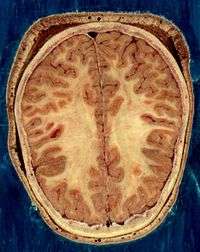

The vertebrate nervous system can also be divided into areas called grey matter ("gray matter" in American spelling) and white matter.[17] Grey matter (which is only grey in preserved tissue, and is better described as pink or light brown in living tissue) contains a high proportion of cell bodies of neurons. White matter is composed mainly of myelinated axons, and takes its color from the myelin. White matter includes all of the nerves, and much of the interior of the brain and spinal cord. Grey matter is found in clusters of neurons in the brain and spinal cord, and in cortical layers that line their surfaces. There is an anatomical convention that a cluster of neurons in the brain or spinal cord is called a nucleus, whereas a cluster of neurons in the periphery is called a ganglion.[18] There are, however, a few exceptions to this rule, notably including the part of the forebrain called the basal ganglia.[19]